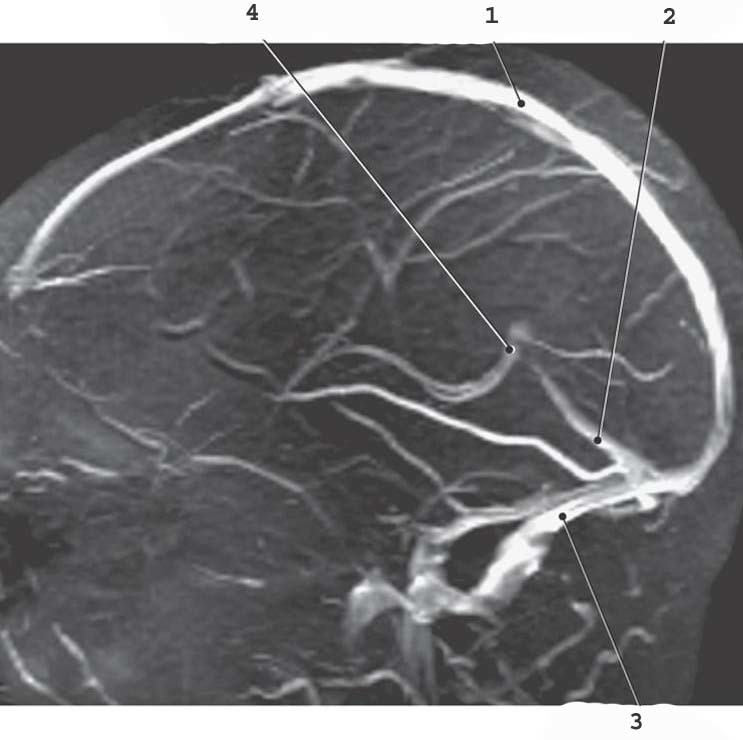

1

Superior Sagittal sinus